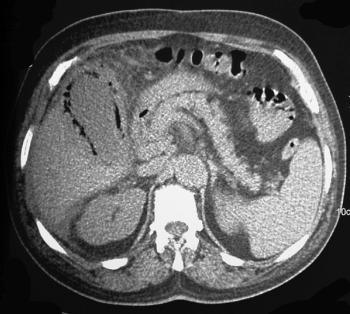

Can you diagnose this patient with unexplained weight loss?